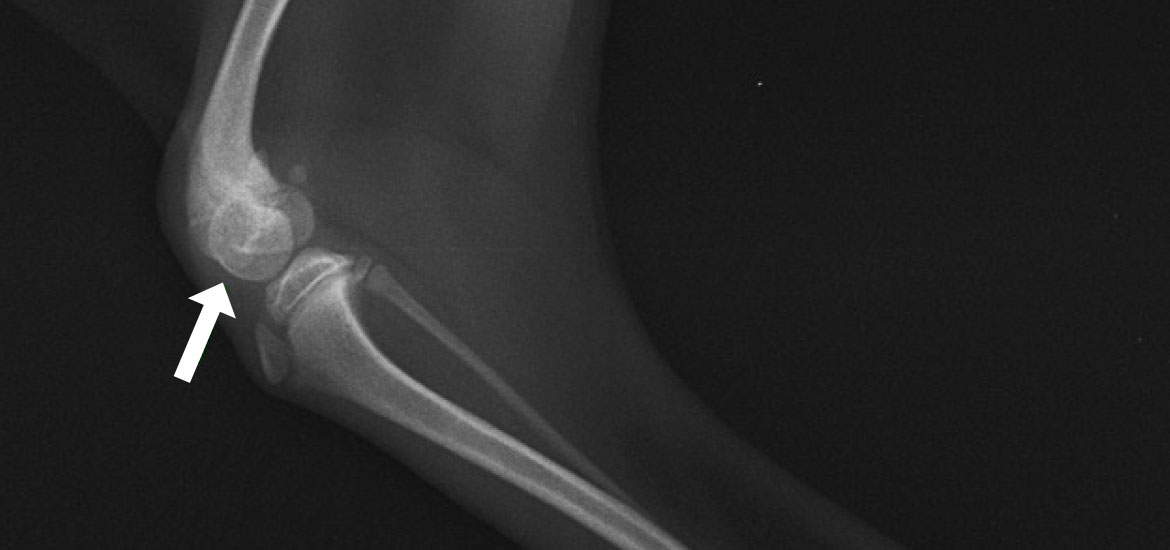

脛骨粗面転位術

けいこつそめんてんいじゅつ

膝関節のパーツが本来の配置・配列になるよう縦軸を矯正。

成長期に脱臼が起きると、膝蓋骨と膝蓋靱帯に引っ張られる形で脛骨もねじれます。その状態で成長すると、脛骨粗面(膝蓋靭帯が付着しているザラザラした部分)がまっすぐ前を向かず、内向きまたは外向きで定着してしまいます。滑車造溝術で溝を造り、脱臼を整復しても、脛骨のねじれをそのままにしておくと、脛骨粗面に付着している膝蓋靭帯が膝蓋骨を引っ張り戻すことになり、再脱臼のリスクが高くなります。

脛骨粗面転移術とは、粗面を膝蓋靭帯が付着したままの状態で骨切りし、大腿骨の溝、膝蓋骨、脛骨粗面が本来の縦一直線で並ぶ正しい位置まで移動させ、ピンで固定させる手術です。膝蓋骨脱臼において、滑車造溝術と組み合わせて施されることの多い術式になります。